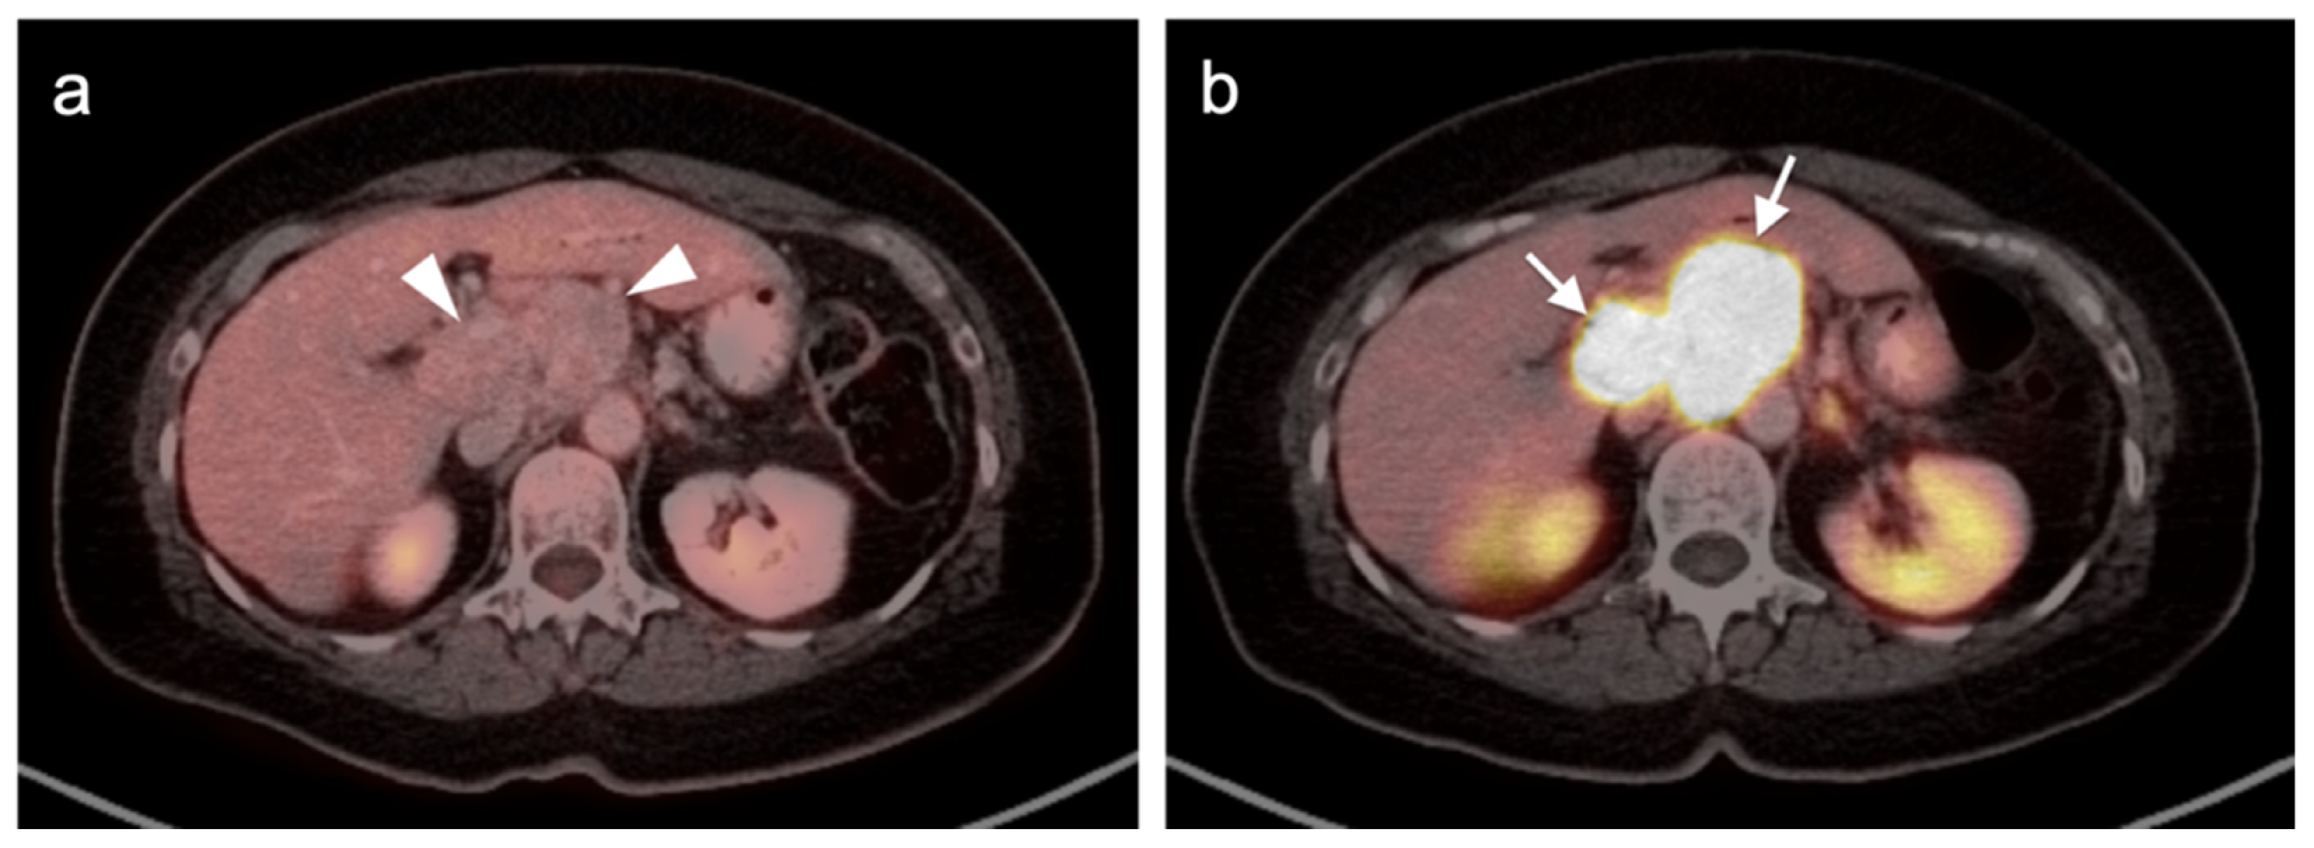

2.3.3. Mucosal Melanoma